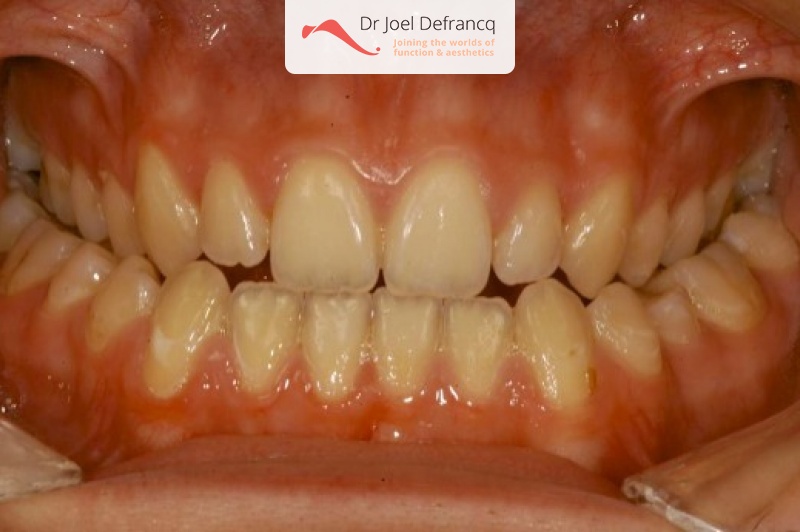

Carmen

Dentale diagnose

- Klasse III